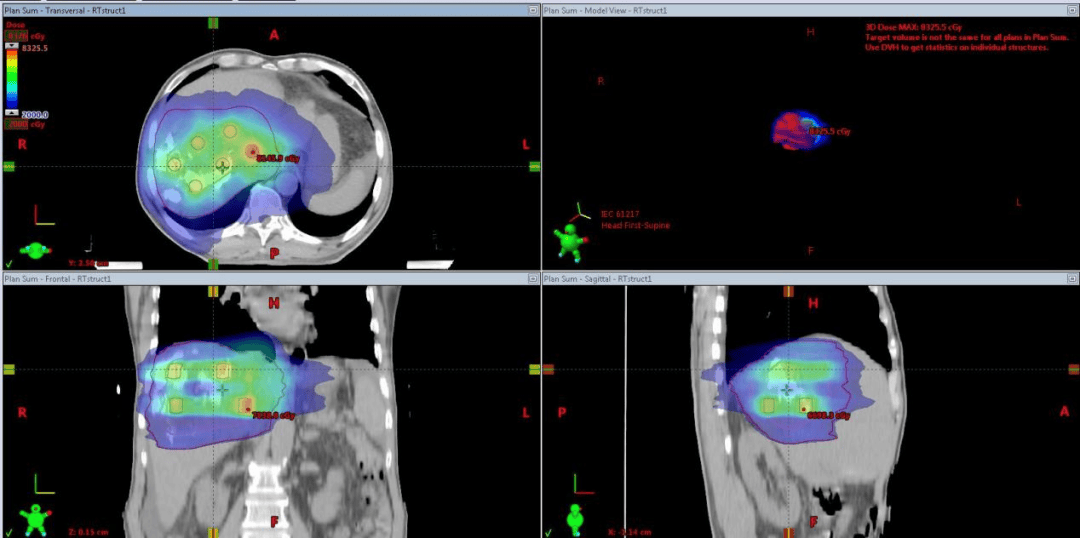

近期,肝胆外科一位患有巨大晚期肝癌并伴有门静脉癌栓的患者,在接受介入治疗及靶免治疗后病情仍有所进展。放疗科在王济东主任的带领下采用创新的晶格放疗(LRT)技术,成功使患者巨大的肿瘤在短期内显著缩小并发